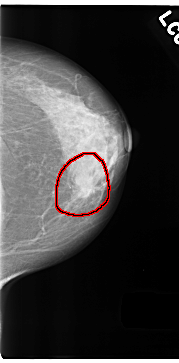

C_0180_1.LEFT_MLO

C_0180_1.LEFT_CC

FILE: C_0180_1.LEFT_CC.OVERLAY

TOTAL_ABNORMALITIES 1

ABNORMALITY 1

LESION_TYPE MASS SHAPE LOBULATED MARGINS SPICULATED

ASSESSMENT 5

SUBTLETY 5

PATHOLOGY MALIGNANT

TOTAL_OUTLINES 1

BOUNDARY